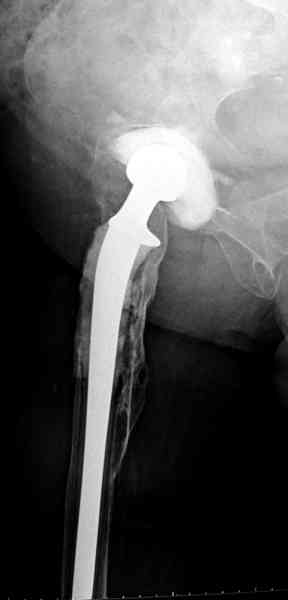

После обработки ацетабулярного компонента, ещё в мягком цементе в полости вертлужной впадины головкой бедренного компонента сделана выемка для головки, чтобы свежий цемент не прилипал к головке. Головку бедренного компонента завернул обычной стерильной фольгой, которую после образования выемки отлепил от головки.

Для спейсера в бедро использовал старый длинный бедренний компонент меньшего диаметра, облепленный со всех сторон цементом с антибиотиком.

Наглухо ушитая рана с дренажом зажила первично, после чего с больной потерял контакт, и только недавно, через 8 лет я осмотрел её. Она без проблем нагружает на конечность и передвигается с помощью трости. От окончательной операции по реконструкции отказывается, довольная результатом.

и последние снимки.